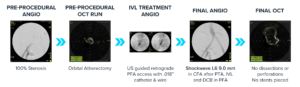

Case courtesy of Prof Stefano Fazzini │ Tor Vergata University │ Rome, Italy

Case courtesy of Mr. Harishankar Nair and Mr. Ashish Patel │ St Thomas’ │ London, UK

Case courtesy of Dr. Mark Portou │ Royal Free │ London, UK